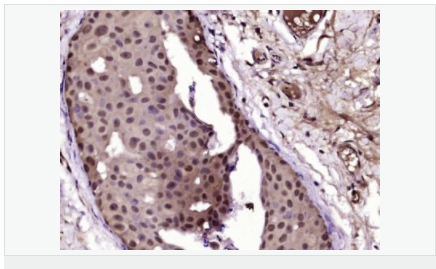

| 英文名稱(chēng) | Progesterone Receptor |

| 中文名稱(chēng) | 孕激素受體抗體 |

| 別 名 | NR3C3; Nuclear receptor subfamily 3 group C member 3; PGR; PR; PRA; PRB; Progesterone receptor; Progestin receptor form A; Progestin receptor form B; PRGR_HUMAN; Progestin receptor form A; Progestin receptor form B. |

| 研究領(lǐng)域 | 腫瘤 免疫學(xué) 信號轉導 生長(cháng)因子和激素 腫瘤細胞生物標志物 |

| 產(chǎn)品應用 | WB=1:500-2000 IHC-P=1:100-500 IHC-F=1:100-500 Flow-Cyt=1ug/Test ICC=1:100-500 IF=1:100-500 (石蠟切片需做抗原修復) not yet tested in other applications. optimal dilutions/concentrations should be determined by the end user. |

| 細胞定位 | 細胞核 細胞漿 |

| 產(chǎn)品介紹 | Estrogen and progesterone receptor are members of a family of transcription factors that are regulated by the binding of their cognate ligands. The interaction of hormone-bound estrogen receptors with estrogen responsive elements(EREs) alters transcription of ERE-containing genes. The carboxy terminal region of the estrgen receptor contains the ligand binding domain, the amino terminus serves as the transactivation domain, and the DNA binding domain is centrally located. Two forms of estrogen receptor have been identified, ER alpha and ER beta. ER alpha and ER beta have been shown to be differentially activated by various ligands. The biological response to progesterone is mediated by two distinct forms of the human progesterone receptor (hPR-Aand hPR-B), which arise from alternative splicing. In most cells, hPR-B functions as a transcriptional activator of progesterone-responsive gene, whereas hPR-A function as a transcriptional inhibitor of all steroid hormone receptors. Function: The steroid hormones and their receptors are involved in the regulation of eukaryotic gene expression and affect cellular proliferation and differentiation in target tissues. Progesterone receptor isoform B (PRB) is involved activation of c-SRC/MAPK signaling on hormone stimulation. Isoform A is inactive in stimulating c-Src/MAPK signaling on hormone stimulation. Subunit: Interacts with SMARD1 and UNC45A. Interacts with CUEDC2; the interaction promotes ubiquitination, decreases sumoylation, and repesses transcriptional activity. Interacts with PIAS3; the interaction promotes sumoylation of PR in a hormone-dependent manner, inhibits DNA-binding, and alters nuclear export. Interacts with SP1; the interaction requires ligand-induced phosphorylation on Ser-345 by ERK1/2 MAPK. Interacts with PRMT2. Subcellular Location: Nucleus. Cytoplasm. Note=Nucleoplasmic shuttling is both homone- and cell cycle-dependent. On hormone stimulation, retained in the cytoplasm in the G(1) and G(2)/M phases. Isoform A: Nucleus. Cytoplasm. Note=Mainly nuclear. Post-translational modifications: Phosphorylated on multiple serine sites. Several of these sites are hormone-dependent. Phosphorylation on Ser-294 occurs preferentially on isoform B, is highly hormone-dependent and modulates ubiquitination and sumoylation on Lys-388. Phosphorylation on Ser-102 and Ser-345 also requires induction by hormone. Basal phosphorylation on Ser-81, Ser-162, Ser-190 and Ser-400 is increased in response to progesterone and can be phosphorylated in vitro by the CDK2-A1 complex. Increased levels of phosphorylation on Ser-400 also in the presence of EGF, heregulin, IGF, PMA and FBS. Phosphorylation at this site by CDK2 is ligand-independent, and increases nuclear translocation and transcriptional activity. Phosphorylation at Ser-162 and Ser-294, but not at Ser-190, is impaired during the G(2)/M phase of the cell cycle. Phosphorylation on Ser-345 by ERK1/2 MAPK is required for interaction with SP1. Sumoylation is hormone-dependent and represses transcriptional activity. Sumoylation on all three sites is enhanced by PIAS3. Desumoylated by SENP1. Sumoylation on Lys-388, the main site of sumoylation, is repressed by ubiquitination on the same site, and modulated by phosphorylation at Ser-294. Similarity: Belongs to the nuclear hormone receptor family. NR3 subfamily. Contains 1 nuclear receptor DNA-binding domain. SWISS: P06401 Gene ID: 5241 Database links: Entrez Gene: 5241 Human Entrez Gene: 18667 Mouse Entrez Gene: 100009094 Rabbit Omim: 607311 Human SwissProt: P06401 Human SwissProt: Q00175 Mouse SwissProt: P06186 Rabbit Unigene: 2905 Human Unigene: 32405 Human Unigene: 742403 Human Unigene: 12798 Mouse Unigene: 437703 Mouse Unigene: 1947 Rabbit Unigene: 10303 Rat Important Note: This product as supplied is intended for research use only, not for use in human, therapeutic or diagnostic applications. |